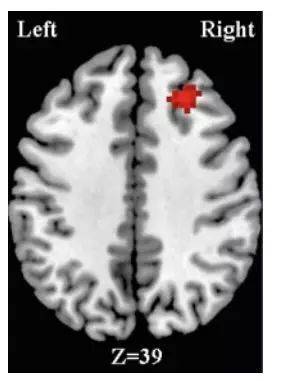

中國科學院的饒麗琳等人通過核磁實驗證明,被試者在選擇基於迷信的決策時,大腦的右側額葉中回的激活程度要低於理性決策時的水平。根據以往的觀察,人們在處理不確定的事件或者處於緊張焦慮的狀態時,大腦的右側額葉中回會異常活躍。

大腦的右側額葉中回活動與迷信決策有關 / 中國科學院饒麗琳等人